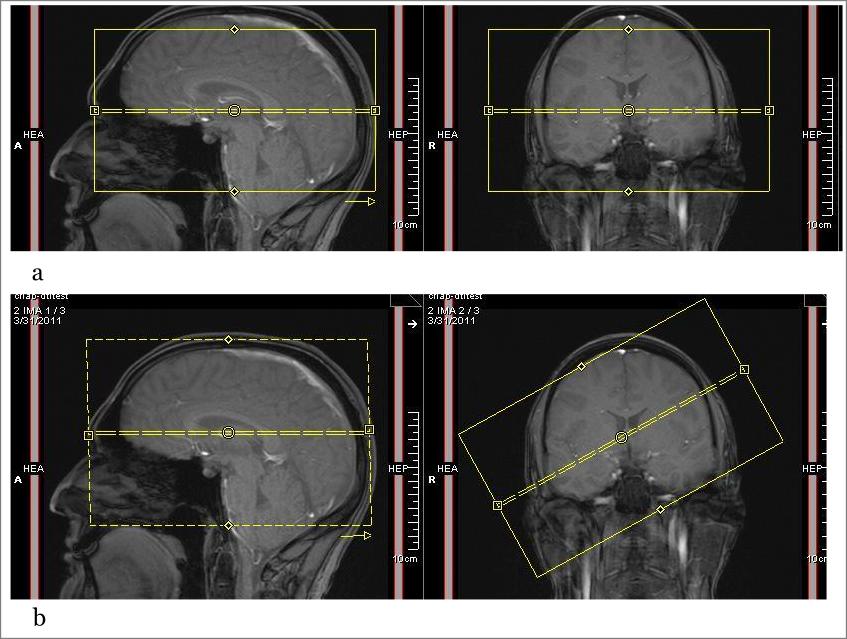

In this tab, the user can specify parameters for running OAR 3D (or OAR 3.5D) algorithm that will perform the rigid registration of B0 to T2 and then DWI to rigidly aligned B0. OAR 3.5D is used to correct the spatial mis-registration of DWI volumes originating from both - subject motion and eddy current-induced distortions. The user has a choice to run OAR 3D or OAR 3.5D. For more information about both algorithms, refer to the OAR documentation.

Clinical diffusion MR studies are mostly based on single-shot echo-planar imaging (EPI) acquisitions. This method is very sensitive to static magnetic field inhomogeneities and artifacts, which appear due to imperfection of the gradient waveforms, and eddy currents during the long readout time. These issues are primarily responsible for creating nonlinear geometric distortion along the phase-encoding direction. Artifacts often appear at air-tissue border and also in the images of the ventral portions of the frontal and temporal lobes. They become even more severe with increasing magnetic field. The mis-registration among a set of DWI volumes due to geometric distortions leads in turn to spatial inaccuracies in the derivation of the diffusion tensor, ADC, and FA since they are typically computed on a pixel-by-pixel basis combining all diffusion-weighting directions.

To correct geometric distortions due to B0 inhomogeneities, MIPAV uses the special image registration technique, where the distorted EPI image is registered to a corresponding anatomically correct MR image with an intensity based least-squares similarity metric and the VABRA modeled deformation field to improve the sensitivity in areas of low EPI signal.